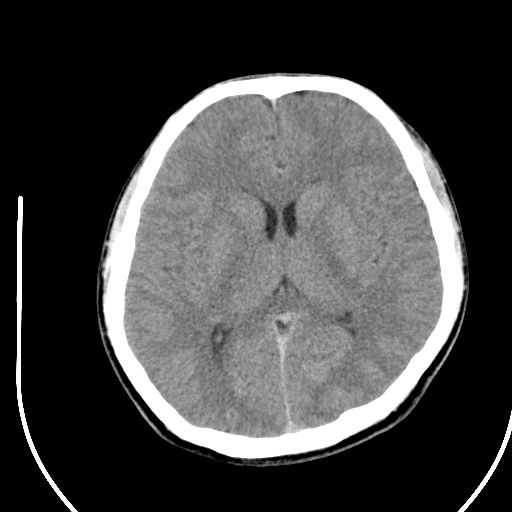

标题: CT28158:男,27Y。头痛数月,左顶叶血管瘤。 [打印本页]

标题: CT28158:男,27Y。头痛数月,左顶叶血管瘤。

海绵状血管瘤

考虑左顶叶海绵状血管瘤,建议mr检查。

左侧额叶海绵状血管瘤可能性大;建议行mri检查。

考虑血管畸形,因其周可见水肿,不除外感染性病灶。建议mri检查。